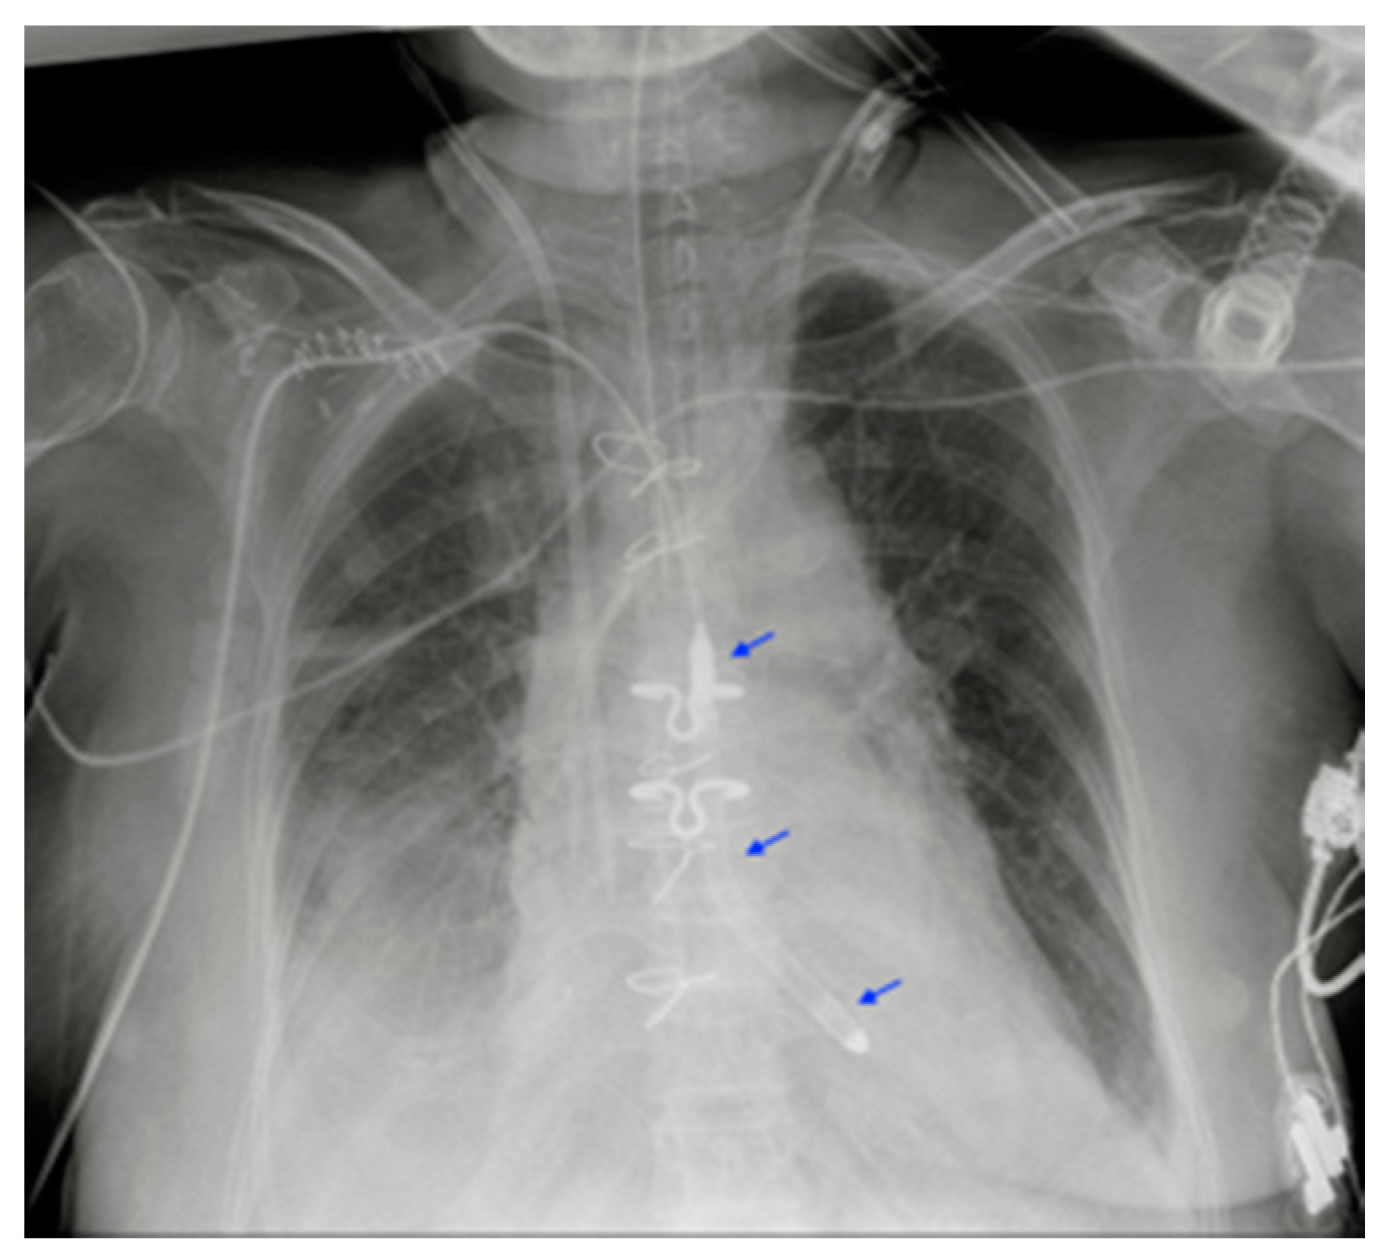

5.5. Intra-Aortic Balloon Pump (IABP)

| IABP | Misposition |